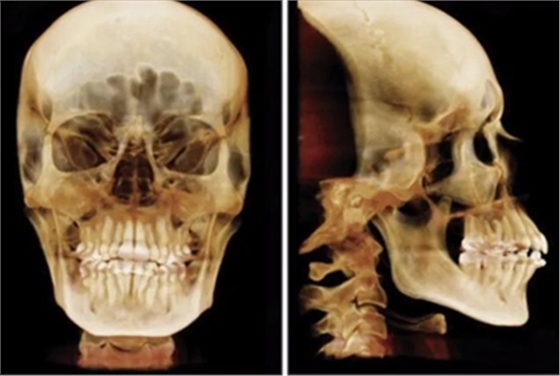

患者曾行正畸治療,現(xiàn)覺(jué)笑容不美觀前來(lái)就診?;颊哒嬗^及側(cè)貌示下頜發(fā)育不足,偏高角,唇閉合不全。上下頜中線(xiàn)齊。覆合、覆蓋4毫米。磨牙關(guān)系及尖牙關(guān)系II類(lèi)。上頜擁擠度4mm,下頜擁擠度6mm。4顆第一前磨牙在第一次正畸治療時(shí)已拔除。上下牙弓呈尖圓型,牙弓狹窄。

頭影測(cè)量分析,SNA角84°,ANB角6°,高角型,詳見(jiàn)下表。